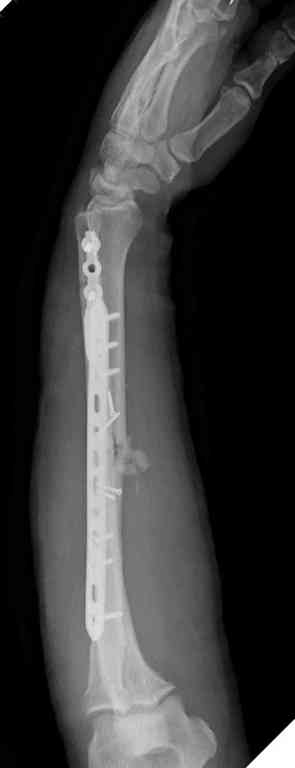

Отечность в зоне фиксации является противопоказанием к открытому методу. Для профилактики осложнений с фиксацией можно повременить применением стабилизирующего наружного фиксатора. Фиксатор восстанавливает длину конечности, облегчает в будущем репозицию и создает благоприятные условии для спадения отека. Также позволяет экономить средства, вместо дорогого стационара больной может находится на амбулаторном наблюдении. Появление симптома "skin wrinkle test" (морщинки) подскажет о готовности кожного покрова для окончательной операции на костях.

Множественная огнестрельная травма конечностей, перелом костей предплечья, фиксация в первые часы и дефект мягких тканей, мероприятия по закрытию...